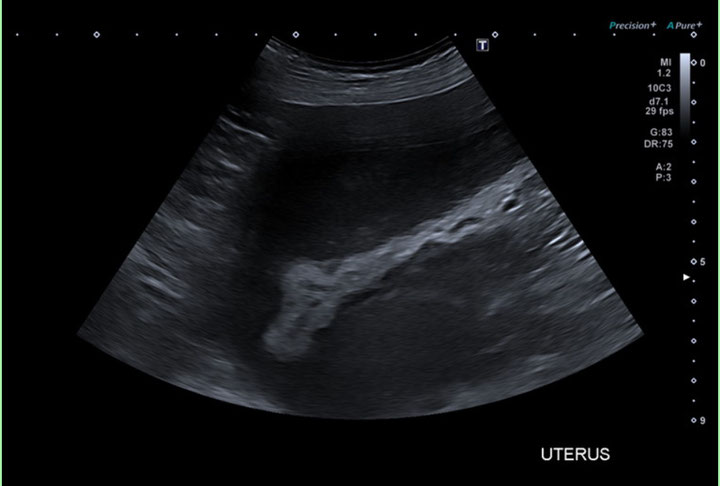

上の画像は、大型犬の子宮をエコー検査所見です。

黒く太い部分が拡張した子宮で、内部に液体(膿)がたまっています。

これは典型的な 子宮蓄膿症(しきゅうちくのうしょう) の所見です。

• レントゲン・エコー検査:子宮の拡張、内部に液体がたまっている様子を確認(今回の画像のように)